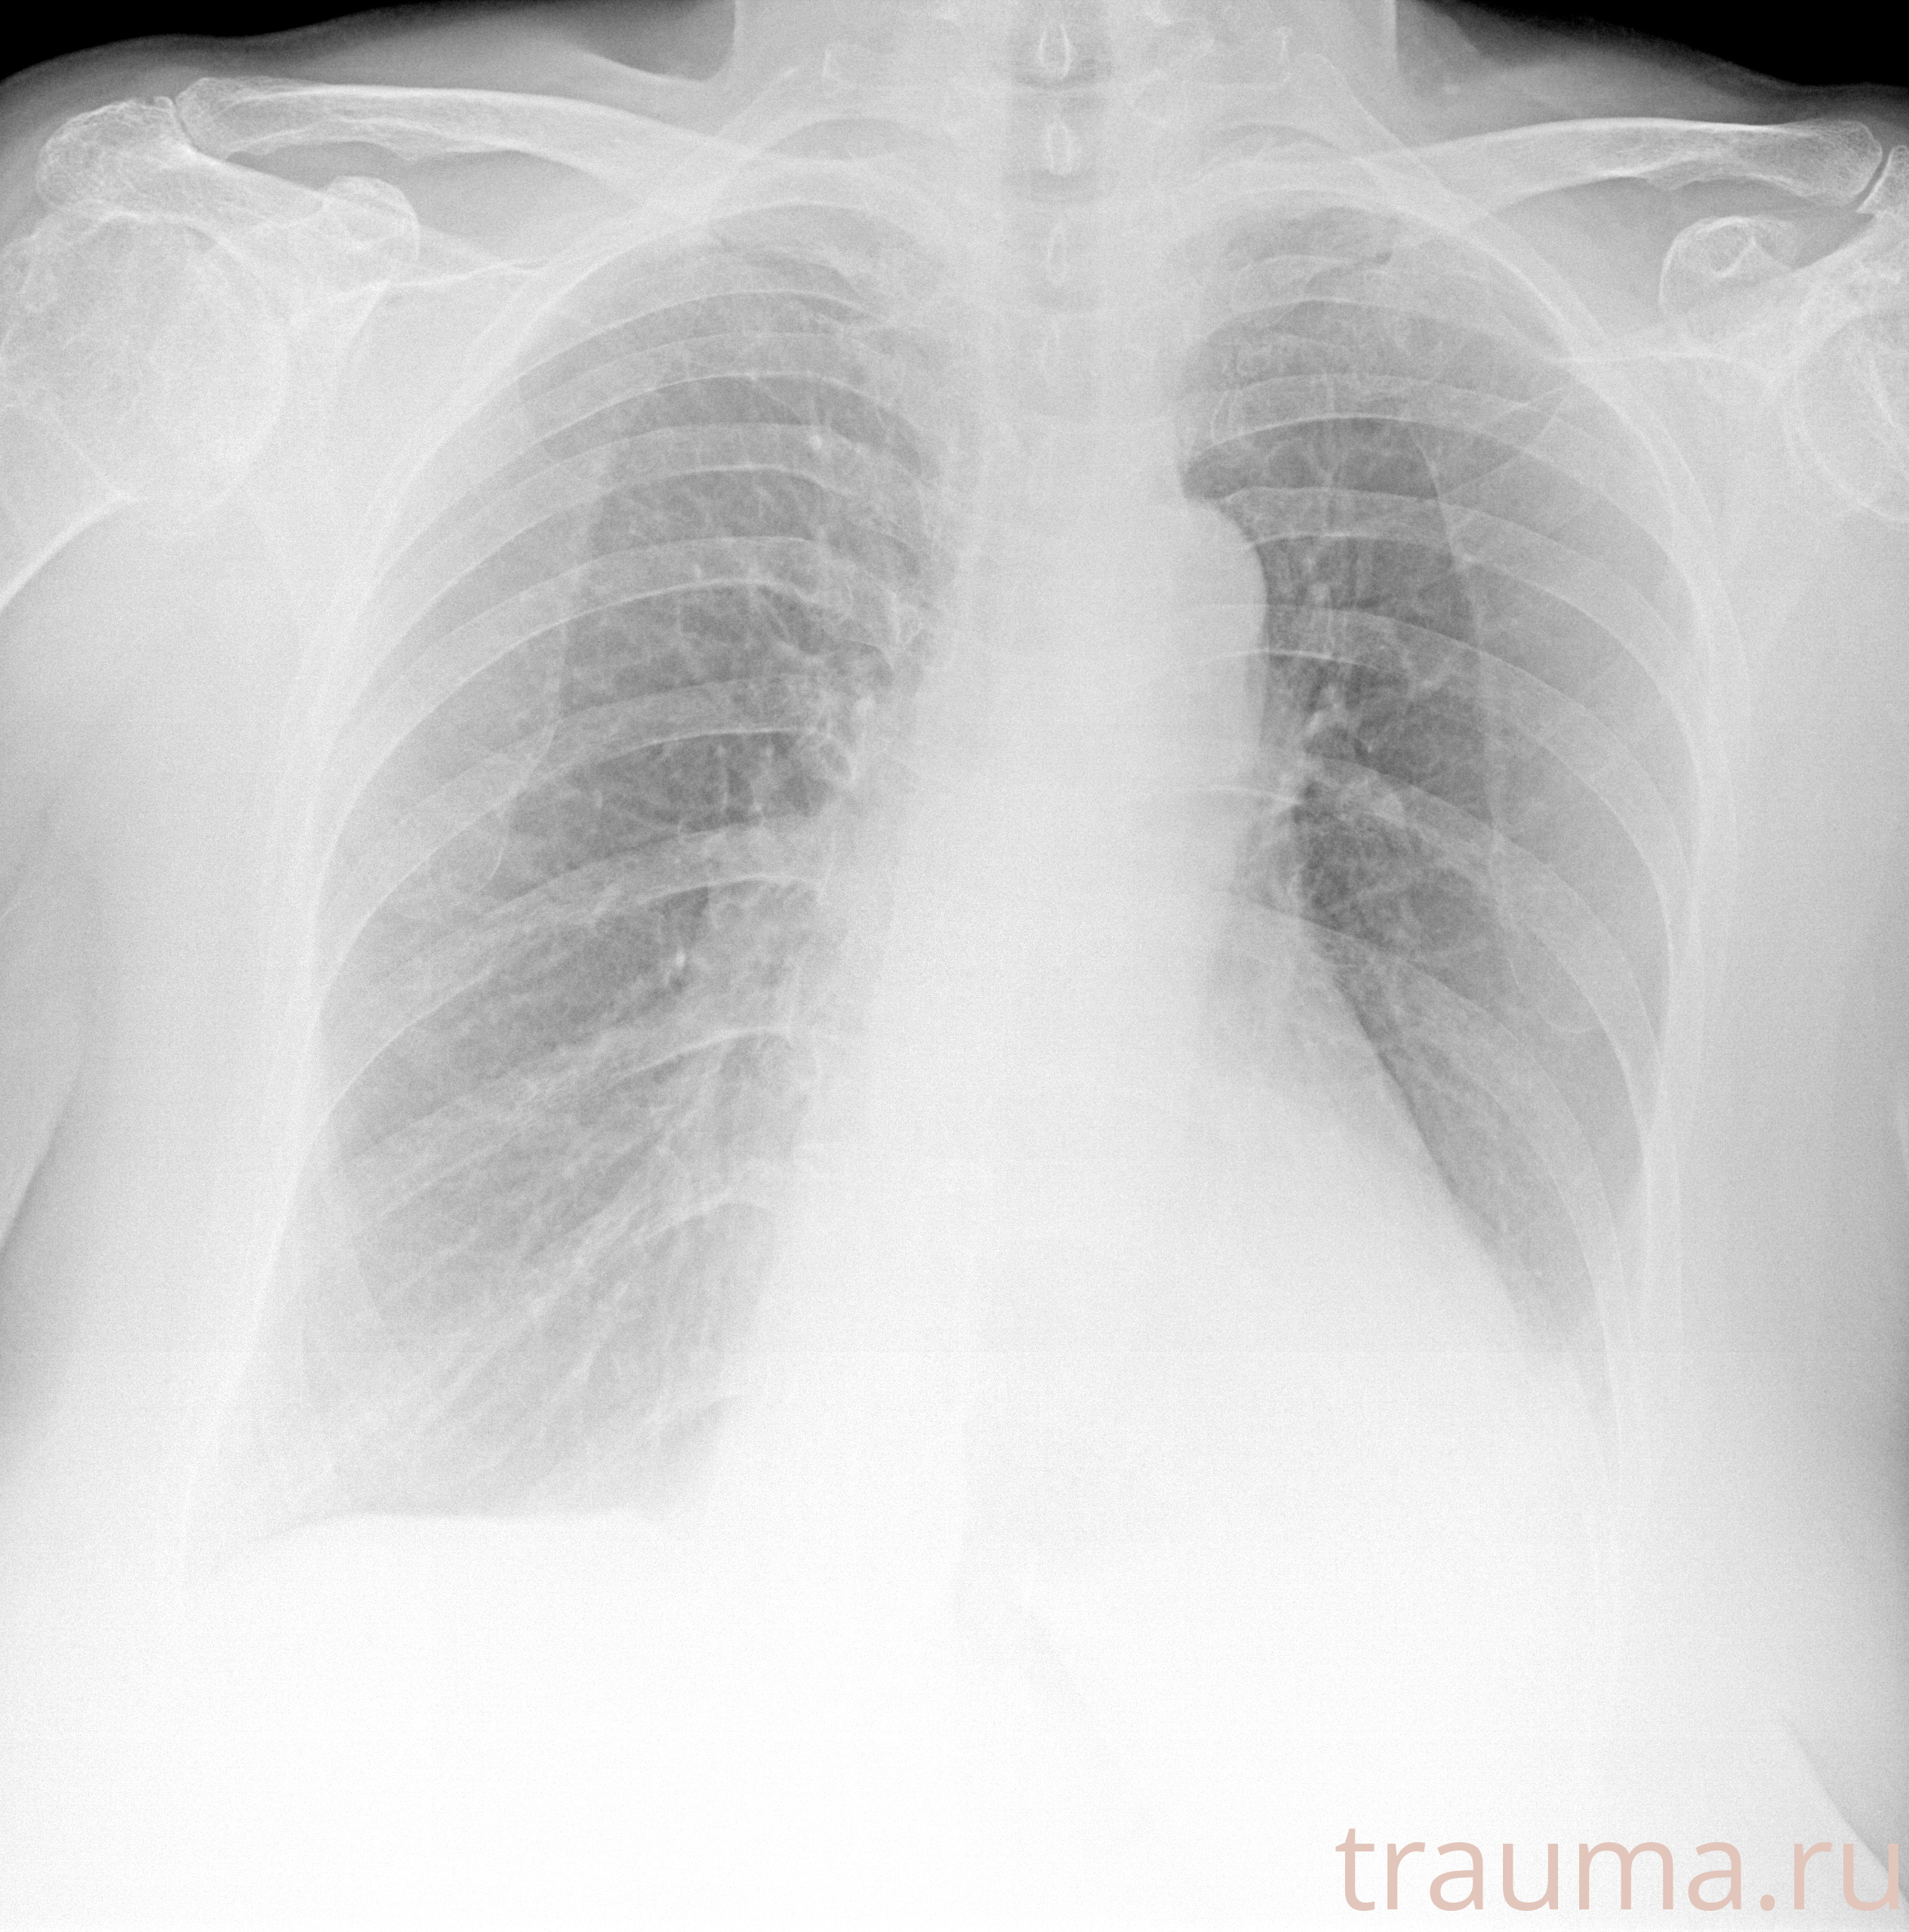

Рентген на дому: по вашему адресу приезжает врач-рентгенолог, травматолог-ортопед с мобильным рентгеновским аппаратом, проводит диагностику травмы или заболевания, делает необходимые рентгенограммы, дает рекомендации по дальнейшему лечению. Получить качественные снимки в домашних условиях возможно благодаря уникальной методике, разработанной МосРентген Центром для института  Склифосовского

при переломе шейки бедра и пневмонии от компании МосРентген Центр - партнера Института имени Склифосовского